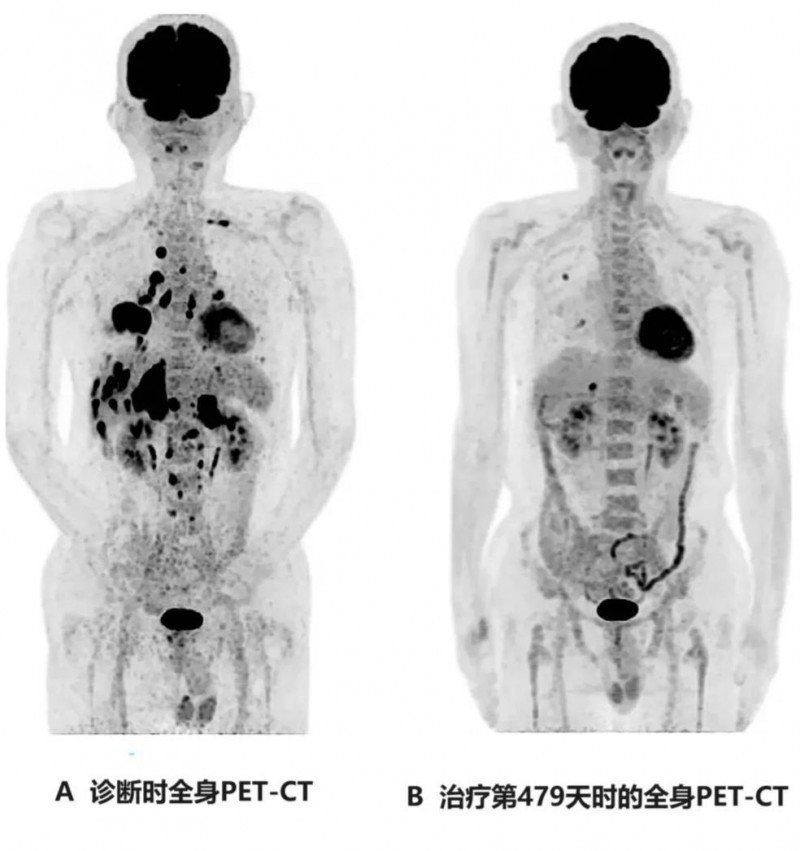

4、全身PET-CT:治疗后第479天,复查全身PET-CT显示,除肝脏转移灶(直径1.7cm)、右肺转移灶(直径1.0cm)外,未见其他异常表现(详见下图)。

图 该患者治疗前后全身PET-CT对比

图A:示右下肺原发肿瘤,伴多发性肝转移、多发性双侧肺内转移、多发性骨转移、双侧肾上腺转移。

图B:示肝脏可见1个小转移灶(直径约1.7cm),右肺见2个小转移灶(直径约1.0cm)。